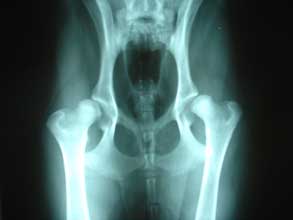

Bilateral Hip Dysplasia

Joel Mills - Creative Commons License

Hip Dysplasia

Hip Dysplasia is a painful condition affecting the hip joints resulting in lameness and arthritis. Although it is hereditary, environmental factors play a role in its development.

In dysplasia the caput (round head of the femur bone) no longer fits snugly into the acetabulum (concave socket in the pelvis). Additionally these two elements, the caput and acetabulum are ill formed and don't move smoothly. This results in undue wear and tear on the joints resulting in the body trying to repair damage by creating cartilage. The body cannot keep up with the rate of degradation and becomes inflammed which contributes to further damage.

As this cycle progresses the dog will become increasingly uncomfortable, eventually being rendered lame due to the intensity of the pain. Signs of this condition will be the dog attempting to restrict movement of their hips, running will appear stilted. This compensation to avoid using the hips can result in spinal or soft tissue problems developing. Hip dysplasia can be anywhere from mild to debilitatingly severe.